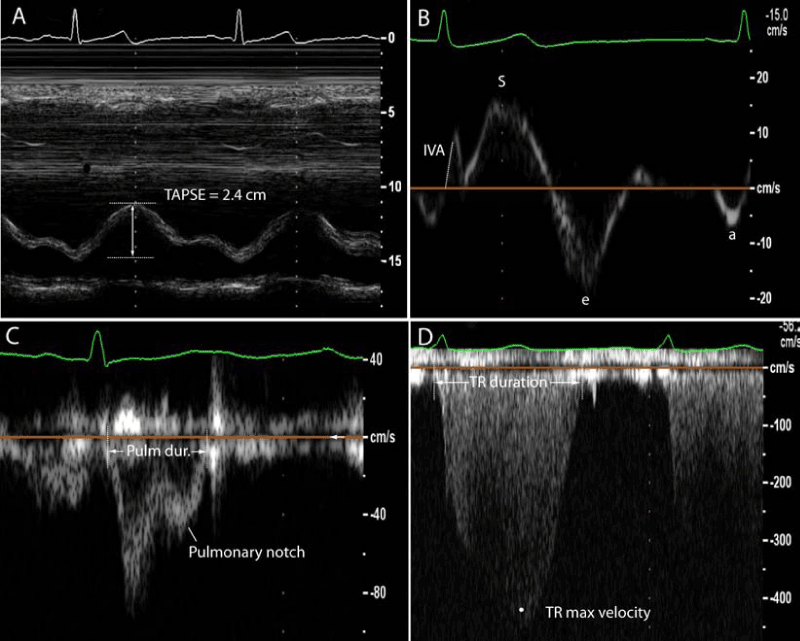

| Figure 2: Selected echocardiographic signals and indices used to measure

right ventricular function and pulmonary flow. Section A shows tricuspid annular plane systolic excursion (TAPSE) in a patient with preserved RV systolic function. Section B shows a tissue-Doppler signal of the proximal right ventricular wall; isovolumic acceleration is measured as the maximal isovolumic velocity divided by the time to peak isovolumic velocity; e is the maximal early diastolic velocity and a represents the maximal late or atrial associated velocity. Section C shows a pulmonary flow signal; a notch is present and usually indicates decreased pulmonary compliance and altered reflection waves. Section D shows a tricuspid regurgitation signal. Both the pulmonary ejection time and the tricuspid regurgitation time are used to measure the right ventricular myocardial performance index (RVMPI). |